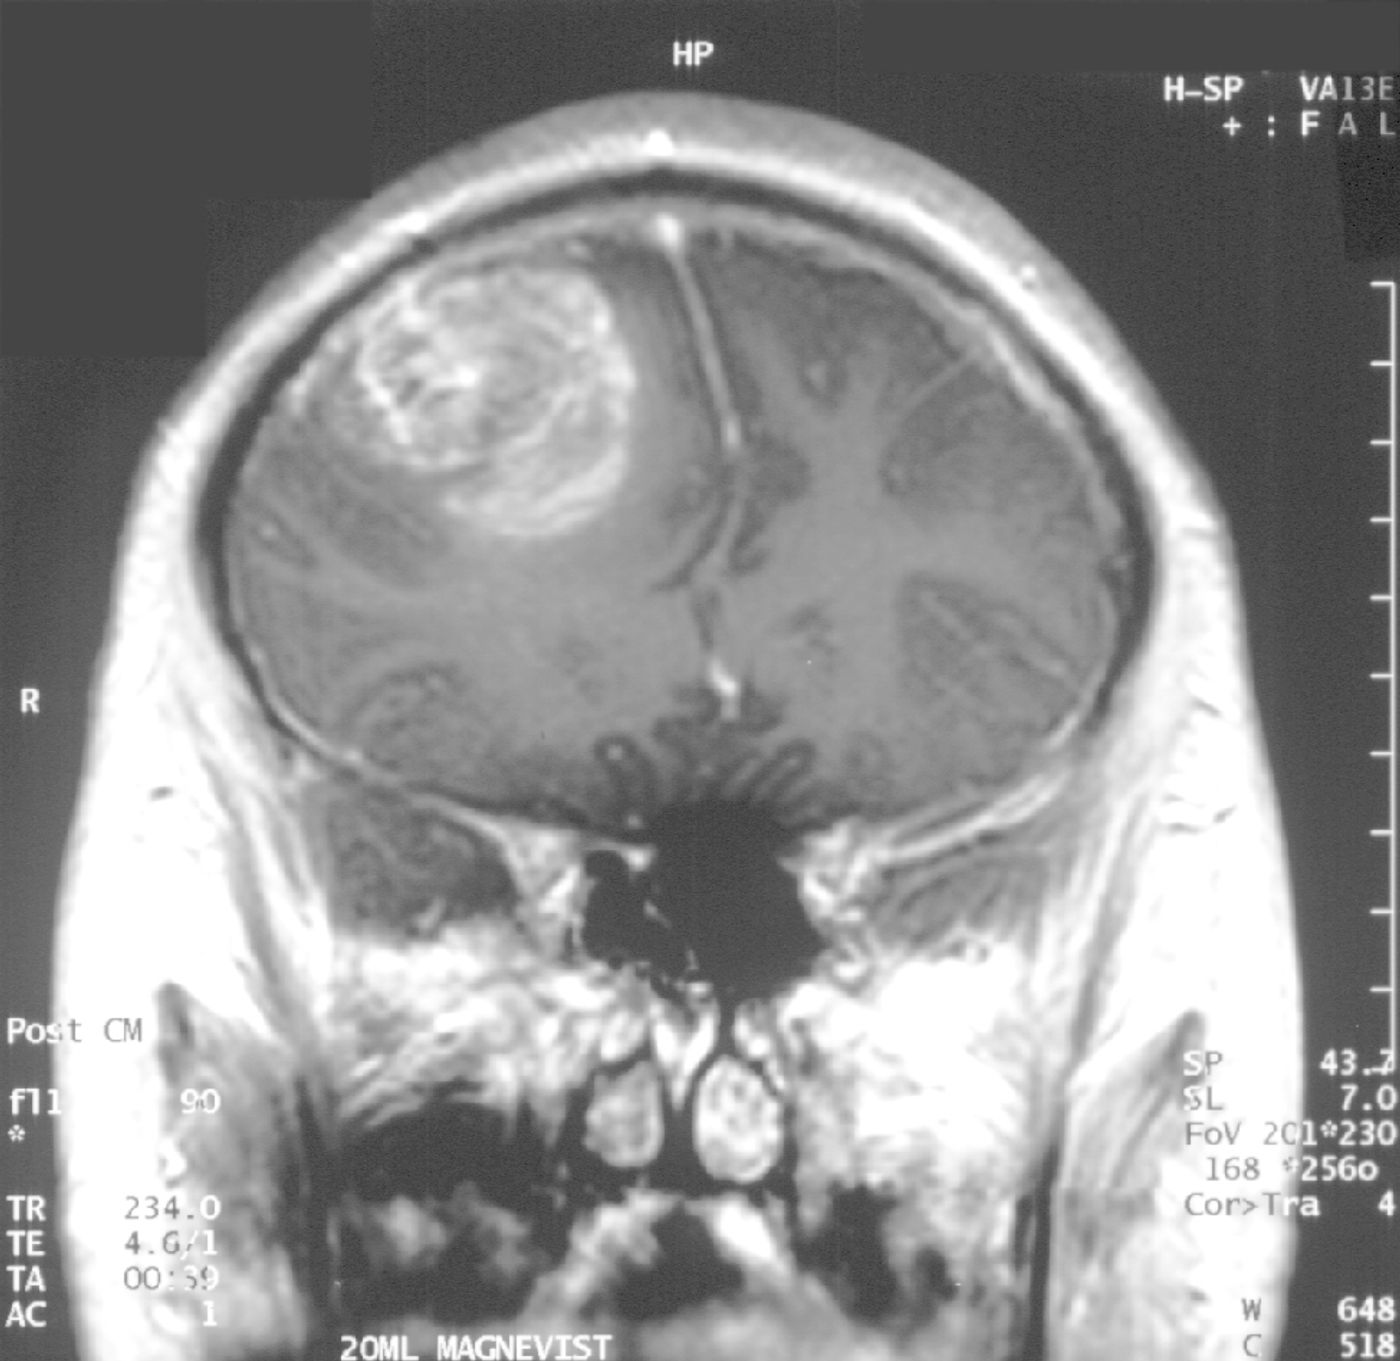

Glioblastoma grade IV.

Glioblastoma patients make up about 15 percent of all those suffering from primary brain tumors. These highly malignant masses are usually discovered in the brain’s cerebral hemispheres, and although this cancer rarely metastasizes, the tumor cells grow rapidly and aggressively. Glioblastoma increases brain pressure, which can cause headaches, nausea, vomiting, and drowsiness. The cause of glioblastoma is unknown.